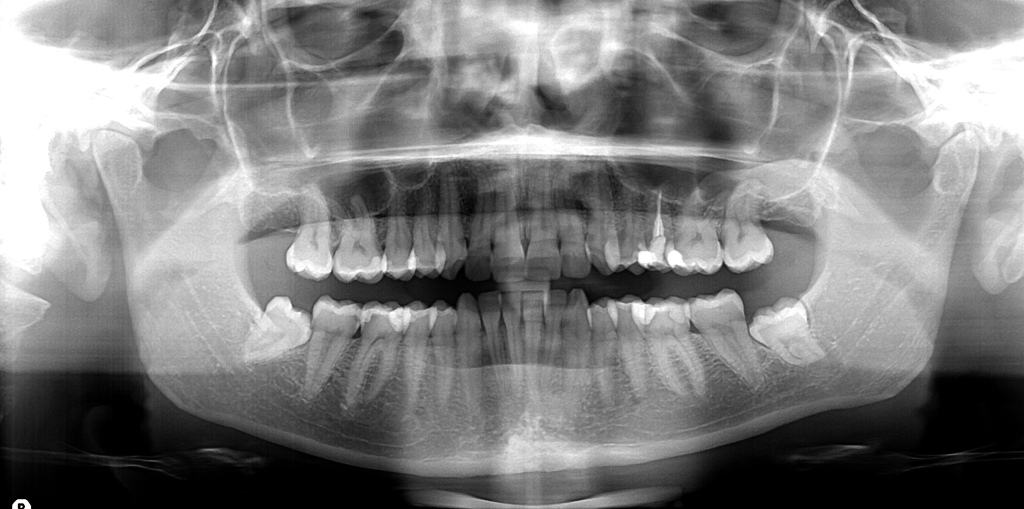

L’ortopantomografia è l’esame radiologico principalmente richiesto ed utilizzato in odontoiatria. Essa permette al dentista di avere la chiara situazione della stato della bocca del paziente. L’ortopantomografia, con una sola scansione veloce, indolore e con relativo basso assorbimento di raggi x.

- avere in un’unica lastra (o videata se si tratta di ortopantomografia digitale) entrambe le arcate dentarie con relativo supporto (mandibola e mascella);

- stabilire le condizioni generali della bocca del paziente aiutando notevolmente il dentista nella formulazione della diagnosi così da individuare la terapia più corretta;

- valutare il processo di dentizione, le ossa mascellari e le articolazioni temporo-mandibolari;

- ispezionare in maniera approfondita lo stato dei denti e scoprire in anticipo eventuali carie nascoste prima che queste possano distruggere buona parte dello smalto della corona, trasformarsi in pulpite e scatenare forti mal di denti;

- esaminare lo stato del parodonto (gengive, legamento parodontale e osso alveolare) ovvero dei tessuti che circondano e sostengono il dente;

Permette l’individuazione e la valutazione del granuloma apicale; - Consente lo studio della diminuzione della densità e della quantità di osso alveolare (che ospita la radice del dente) a causa di infiammazione (osteolisi alveolare);

- Ortopantomografia è anche il primo esame a scopo di indagine nel caso di dente del giudizio ritenuto;

- Conoscere la posizione e l’ampiezza dei seni paranasali, la posizione dei forami mentonieri (molto importante per la messa in opera della tecnica ALL-ON-4 e per il posizionamento dei mini-impianti dentali.); conoscere il percorso del nervo alveolare;

- Individuare cisti o tumori;